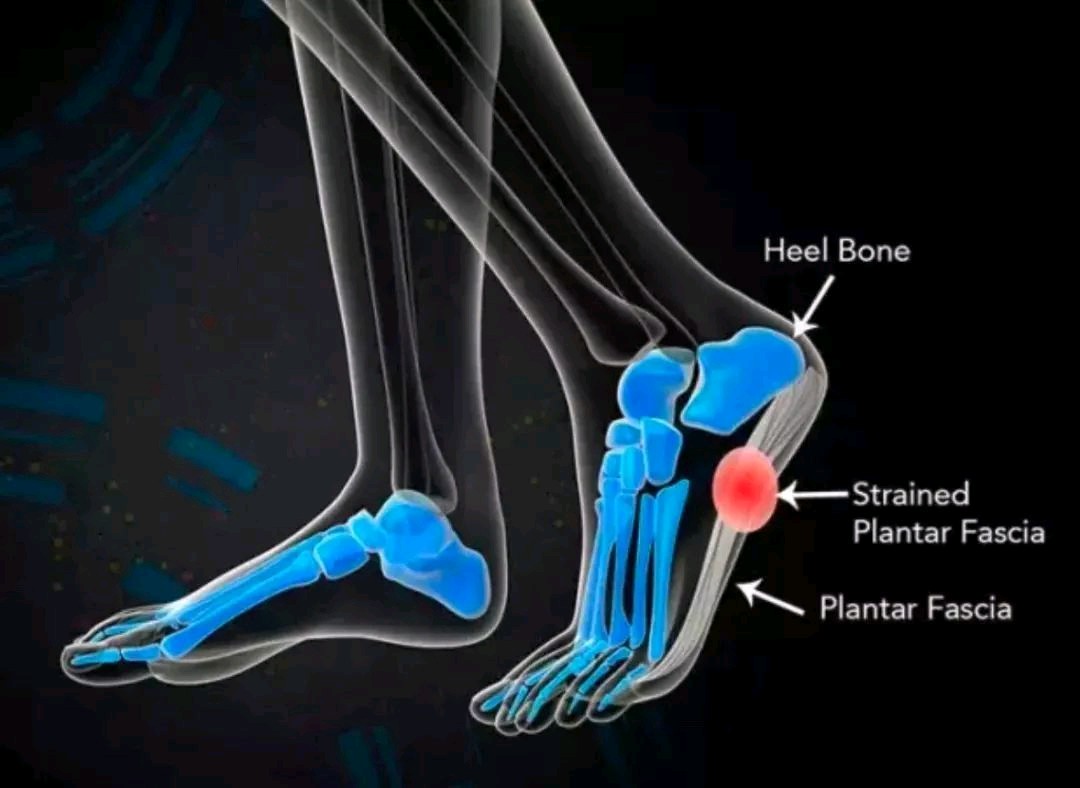

足底筋膜炎是一种常见的足部疾病,主要表现为足底疼痛,尤其在早晨起床或长时间站立、行走后更加明显。这种疼痛可能会影响日常生活,如行走、跑步和站立等。本文将详细介绍足底筋膜炎的病因、症状、诊断和治疗方法。

足底筋膜炎的典型症状是足底疼痛,通常位于足跟或足底中部。疼痛在早晨起床时最为明显,行走一段时间后可能会减轻,但随着活动增加,疼痛可能会再次加剧。此外,患者还可能出现足部肿胀、僵硬和骨刺等症状。